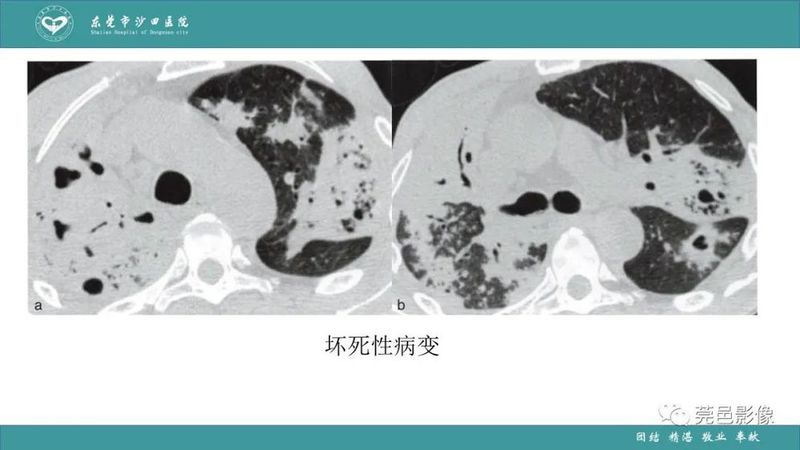

「肺炎克雷伯杆菌肺炎」影像学诊断+鉴别诊断